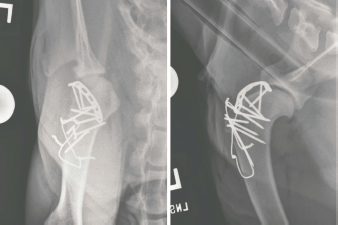

The dog was reexamined at the UF SAH 14 months following the surgery to obtain long-term functional results of the procedure (Cook et al., 2010). The owner reported the dog had resumed all normal activities without lameness. On examination, the dog ambulated without appreciable lameness. The dog was walked over a force platform (Model# OR6-6-1000; Advanced Mechanical Technology, Newton, MA) and mild asymmetry between the thoracic limbs was recorded. The peak vertical force (100*N/kg body weight) and vertical impulse for the left thoracic limb were 5% and 6% lesser than the right thoracic limb. The left scapulohumeral joint was comfortable on palpation and could not be luxated. The dog was sedated (dexdomitor 350 mcg IV and butorphanol 0.1 mg/kg IV) and radiographs of the left scapulohumeral joint were obtained (Fig. 7). The left scapulohumeral joint was congruent and there was minor osteophyte formation on the caudal and lateral aspects of the glenoid cavity. Three out of the four bone screws engaging the bone plate along the proximal humerus had broken; there was moderate sclerosis of the humeral head and neck; and the humeral cortex at the level of the third most distal screw was irregularly marginated, decreased in mineral opacity, and ill-defined. The greater tubercle osteotomy had obtained union. While sedated, left forelimb circumference and joint flexion and extension angles were measured. There was mild muscle atrophy of the left thoracic limb: the circumference of the left brachium was 22.3 cm (right: 23.1 cm) and the left antebrachium was 14.1 cm (right: 14.5 cm). While flexion of the left scapulohumeral joint was now equal to the right (both 37°), extension of the left scapulohumeral joint was improved (145°), but still limited as compared to the right (170°). Extension (152°) and flexion (18°) of the left elbow had also improved and were comparable to the right elbow (extension 161°; flexion 16°).

Fig. 7. Caudocranial (left) and mediolateral (right) projections of the left scapulohumeral joint made 14 months following the surgery. The scapulohumeral joint is congruent. Three bone screws engaging the contoured bone plate are fractured, and there is sclerosis of the femoral head and neck. The humeral cortex at the level of the third most distal screw is decreased in mineral opacity and ill-defined.